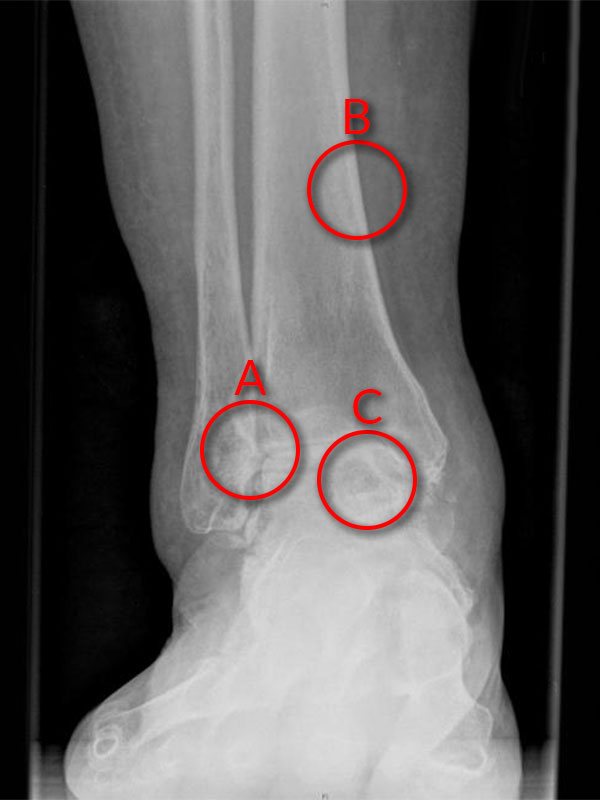

Ankle replacement surgery is an option for end stage ankle arthritis. This may have been discussed with you or planned for your ankle arthritis problem.

(A: Loss of cartilage in joint space - ‘bone on bone’ arthritis, B: Tibia, C: Talus.)

One recent study showed that people with end stage ankle arthritis suffer just as much pain and disability as people with end stage hip arthritis (not surprising really).